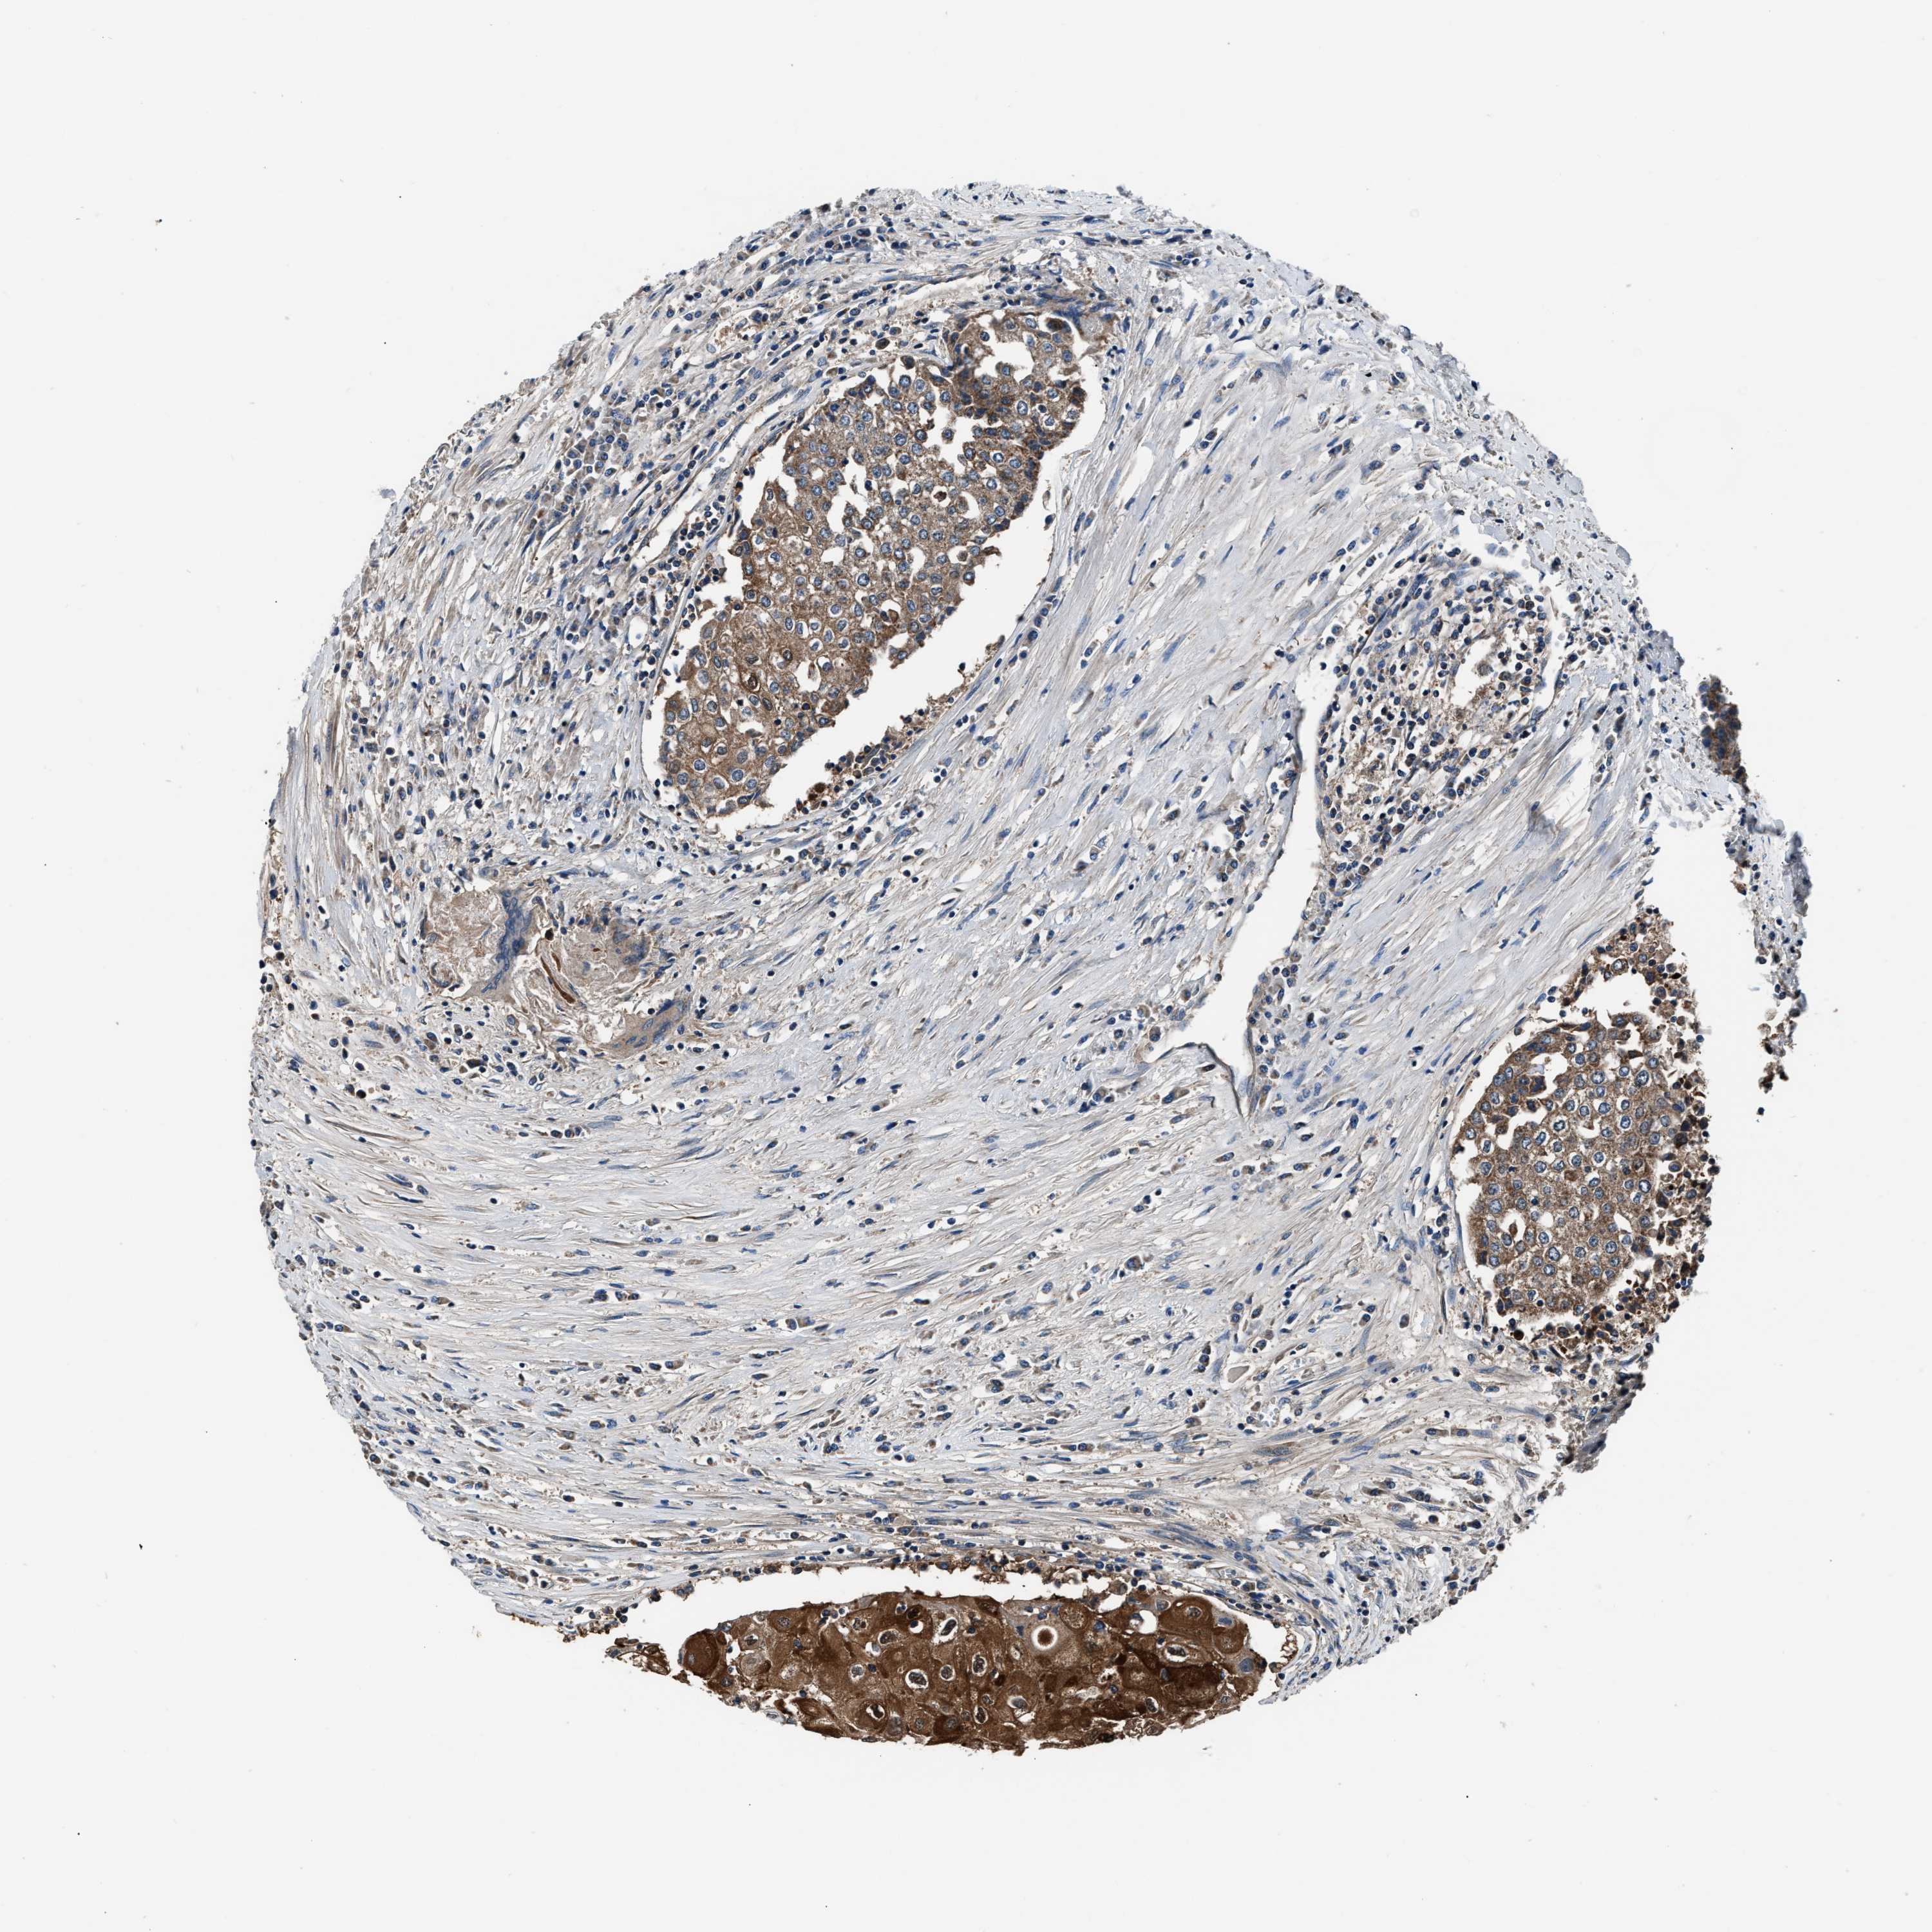

UROTHELIAL CANCER - Protein expressioni

A mouse-over function shows sample information and annotation data. Click on an image to view it in a full screen mode. Samples can be filtered based on level of antibody staining by selecting one or several of the following categories: high, medium, low and not detected. The assay and annotation is described here.

Note that samples used for immunohistochemistry by the Human Protein Atlas do not correspond to samples in the TCGA dataset.

Antibody stainingi

Antibody staining in the annotated cell types in the current human tissue is reported as not detected, low, medium, or high, based on conventional immunohistochemistry profiling in selected tissues. This score is based on the combination of the staining intensity and fraction of stained cells.

Each image is clickable and will lead to virtual microscopy that enables deeper exploration of all samples and also displays staining intensity scores, fraction scores and subcellular localization as well as patient and tissue information for each sample.

Antibody HPA020735

Staining

High

Medium

Low

Not detected

Intensity

Strong

Moderate

Weak

Negative

Quantity

>75%

75%-25%

<25%

None

Location

Urothelial carcinoma, Low grade

Urothelial carcinoma, High grade